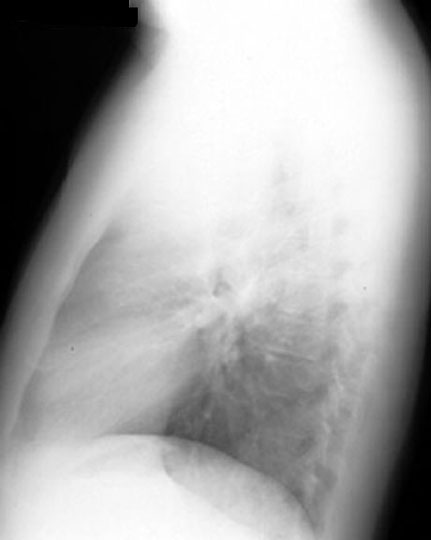

48 year old female presents with low grade fever, dry cough and 12 lbs weight loss in the past two months.

Findings:

• Mediastinal adenopathy

• Particularly in anterior mediastinum

• Bilateral and asymmetric

• Large and bulky

Diagnosis

Anterior Mediastinal Mass

Lymphoma